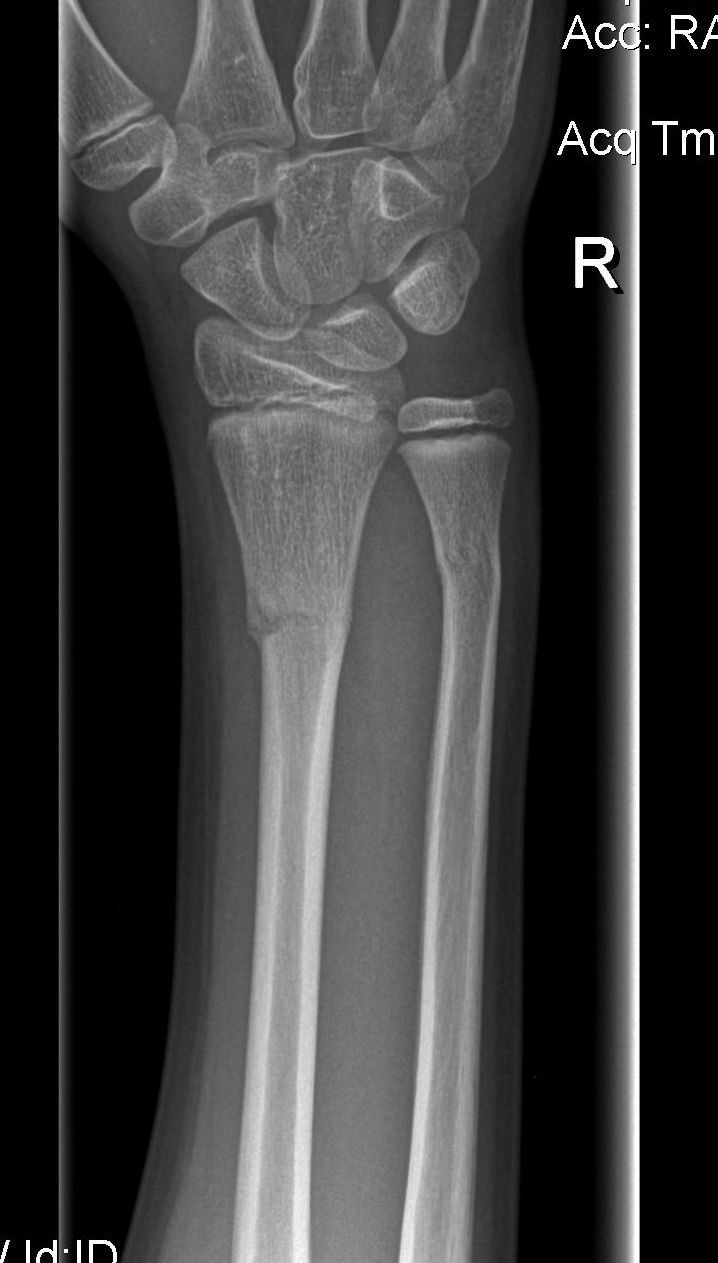

Nikhil broke his arm last week – both radius and ulna. He’ll be in a cast for the next 4 weeks. Fortunately, no surgery needed but the first few days are quite painful.

At the hospital, they now send you home with a CD of x-ray pictures. This is cool – no more films.